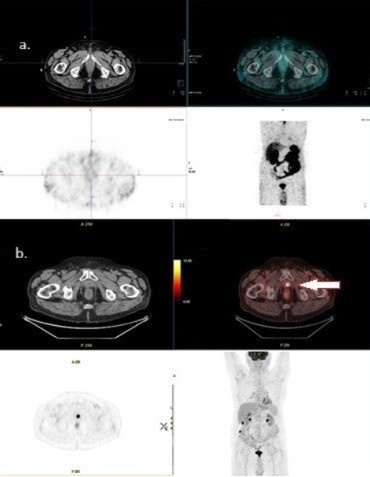

2.4. PSMA-Targeting Radiopharmaceutical PET/CT